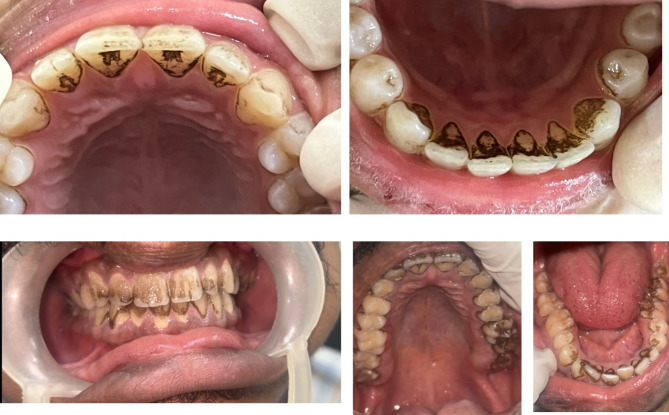

Chromogenic staining is a type of extrinsic staining of teeth caused by certain color producing bacteria. Bacterial organisms cause a variety of color changes on the teeth surfaces ranging from green, black, brown to orange. These stains have been reported to affect primary dentition and permanent dentition [5–7]. These color changes and patterns in clinical presentations are peculiar in case of chromogenic staining (Fig. 1). These stains are noted along the cervical thirds of the teeth in the form of confluent dots. In routine clinical practice, it has been found that they are resistant to the conventional treatment modalities. They reappear to cause staining in a span of weeks to months [8]. Hence this scoping review aimed to explore the various etiological, clinical characteristics and treatment of chromogenic staining of teeth and the various management strategies reported in the literature.

Fig. 1.

Clinical photographs of patients with chromogenic staining of anterior and posterior teeth